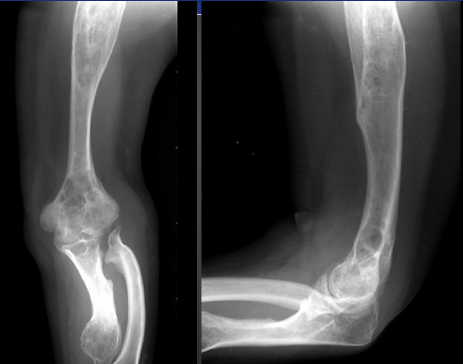

Hereditary Multiple Exostoses

-AKA osteochondromatosis

-Multiple osteochondromas that may cause severe boney deformity

-80% discovered by 10 years of age

Clinical Presentation of Hereditary Multiple Exostoses

-5 to 25% malignant degeneration

-Possible symptoms associated with deformity

Distribution of Hereditary Multiple Exostoses

-Knee

-Ankle

-Shoulder

-Hip

-Wrist (madelung-like deformity)

HME on X-ray

Brahma Bull Appears (HME) on X-ray

Madelung-like Deformity on X-ray (HME)